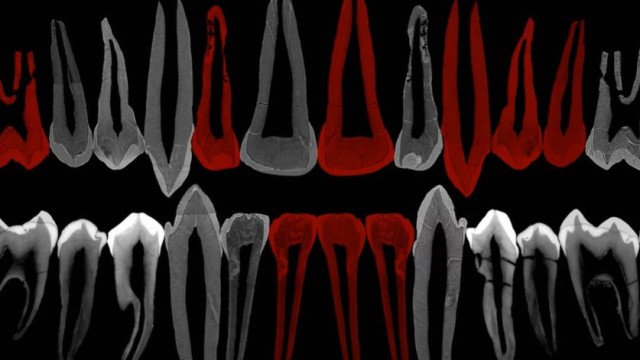

Análises detalhadas dos fósseis do jovem, feitas por meio de microtomografias, indicam que seus dentes se formavam num ritmo intermediário entre o das crianças modernas, muito lento e gradual, e o de chimpanzés e outros grandes símios, que já ganham boa parte de sua dentição definitiva nos primeiros anos de vida. Os detalhes do processo podem não parecer muito significativos, mas eles trazem uma série de possíveis implicações para a compreensão do desenvolvimento cognitivo e social dos ancestrais da humanidade.

Com a ajuda de uma das formas mais sofisticadas de tomografia disponíveis para a ciência, conduzida num acelerador de partículas em Grenoble, na França, Zollikofer, Ponce de León e seus colegas conseguiram enxergar as camadas de formação do dente ao longo da vida do adolescente.

O que acontece é que, num ritmo diário, os dentes que estão crescendo recebem novas camadas de dentina (mais funda) e esmalte (mais superficial), até adquirir seu formato “pronto”. Isso corresponde a linhas de crescimento que a microtomografia é capaz de divisar. E, a partir disso, os pesquisadores estimam qual teria sido o ritmo de formação dos dentes, o que corresponde, indiretamente, à idade do indivíduo.

Além disso, o ritmo geral do desenvolvimento dos dentes se revelou bastante significativo. Os chimpanzés, nossos parentes vivos mais próximos, têm um pico de formação dos dentes muito cedo, com dois anos de vida. Nos humanos modernos, o pico vem apenas aos sete anos de idade, depois de começar muito devagar e de perder velocidade depois. Já o padrão do jovem georgiano também começa lento, só que alcança um pico antes, aos cinco anos, e também termina antes, num momento não muito diferente do visto entre os chimpanzés.